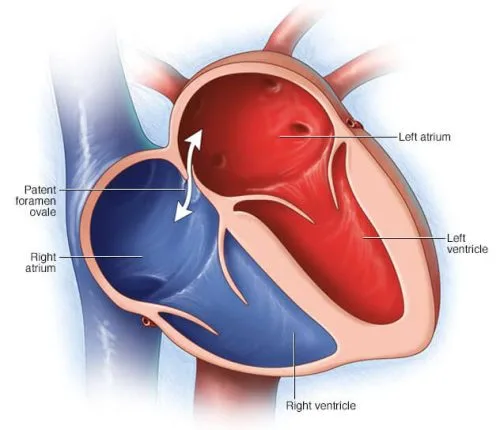

- 2018 AHA/ACC Guideline for the Management of Adults With Congenital Heart Disease

- 2018 AHA/ACC Guideline for the Management of Adults With Congenital Heart Disease

- قلب چیست